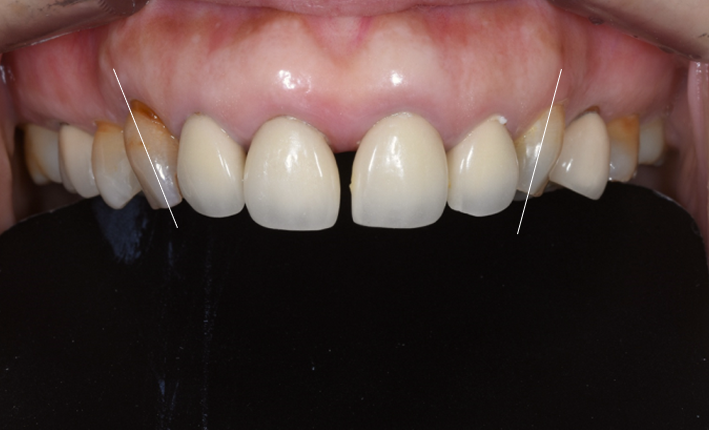

최종 결과 – 자연스럽고 조화로운 앞니 완성

최종 보철 완성 – 모든 치아가 자연스럽게 정리된 모습. 가운데 두 앞니는 연결 크라운으로 제작했습니다

약 3개월간의 임시 크라운 기간을 거친 후, 환자분이 다시 한국에 방문하셨을 때 최종 PFZ 크라운 6개를 세팅했습니다.

치료 전후를 비교하면 다음과 같은 개선이 이루어졌습니다.

| 치아 사이 검은 삼각형 공간(블랙트라이앵글) | 블랙트라이앵글 대폭 개선 |

| 앞니 사이 벌어진 공간 | 공간 해소, 가지런한 배열 |

| 크라운 변색, 색상 부조화 | 자연스럽고 균일한 색조 |

| 크라운 마진 부적합 | 정밀한 마진 적합 |

| 앞니 사이 다시 벌어질 위험 | 연결 크라운으로 재벌어짐 방지 |

| 입술 돌출 우려 | 평탄한 크라운 윤곽으로 입술 라인 개선 |

아랫니와도 자연스러운 조화를 이루는 모습